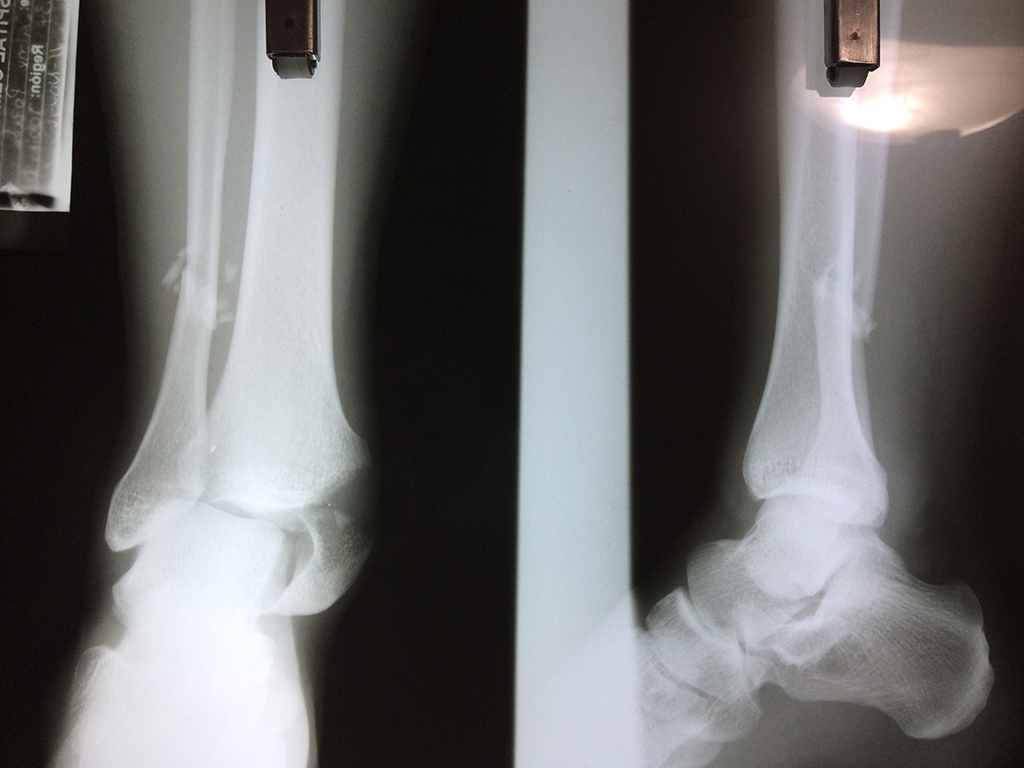

Una fractura de tobillo es la rotura de uno o más de los huesos del tobillo. Estas fracturas pueden ser:

Algunas fracturas de tobillo pueden requerir cirugía si:

- Los extremos de los huesos están desalineados entre sí (desplazados).

- La fractura se extiende hasta la articulación del tobillo (fractura intra-articular).

- Los tendones o ligamentos (tejidos que sujetan los músculos y los huesos entre sí) están rotos.

- El médico cree que sus huesos probablemente no sanen apropiadamente sin cirugía.

- El médico considera que la cirugía puede permitirle una recuperación más rápida y confiable.

- En los niños, la fractura involucra la parte del hueso del tobillo donde el hueso está creciendo.